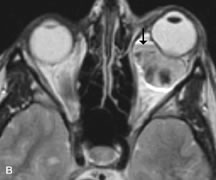

Pleomorphic adenomas demonstrate long T1 and T2 signal characteristics. They may show heterogeneity on T2-weighted images74 and moderate to marked enhancement with contrast.75 Signal characteristics of adenoid cystic carcinoma include hypointensity to fat on T1-weighted images, hyperintensity to fat with increased T2 weighting, and isointensity to fat on proton density-weighted studies (Fig. 23).31,75 Secondary bony alterations of the lacrimal fossa associated with lacrimal gland tumors, such as remodeling (benign mixed tumor) or destruction (adenoid cystic carcinoma), are seen indirectly on MR images; however, bone windows on CT scans provide better delineation of these changes. In contrast to the round or globular appearance of benign or malignant epithelial tumors of the lacrimal gland, lymphoproliferative tumors usually appear to be molding or draping onto the globe and the surrounding bony orbit.

Fig. 23. A. T2-weighted and (B and C) postcontrast fat-suppressed T1-weighted MR scans demonstrate an infiltrative lacrimal region mass than invades the lateral rectus muscle (arrows). This highly cellular lesion is seen to have a very hypointense appearance on the T2-weighted scan.